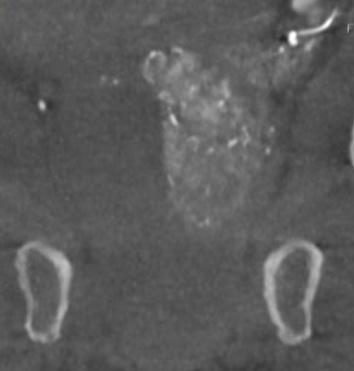

The incidence of lung cancer has increased considerably in the last few decades with the lung as the most common site of metastatic involvement. Despite the improvements in the diagnosis and treatment for malignant lung tumours, the prognosis of the patients is still unsatisfactory.1 Currently, locoregional chemotherapeutic techniques such as transpulmonary chemoembolization (TPCE) for the treatment of lung malignancies have gained increasing importance. The purpose of this retrospective study was to evaluate local tumour response and patient survival after the treatment of pulmonary metastases using TPCE as a palliative treatment method.

In TPCE, a 5 French (Fr) endovascular sheath and 5Fr headhunter catheter are routinely placed transfemorally under fluoroscopy until the pulmonary artery and subsequently the tumourfeeding segmental pulmonary branch are reached. A balloon catheter (up to 7mm in diameter) is optionally placed for better results.2 This selective pulmonary artery catheterisation results in a blockage of the arterial supply to the tumour tissue, resulting in regional ischaemic necrosis in the target tumour tissues while reducing damage to the surrounding normal lung parenchyma. Thereafter, mitomycin

and gemcitabine as chemotherapeutic agents are administered in combination with an embolization of lipiodol and microspheres. This extends the storage time of the injected cytostatics in the tumours and reduces the outflow into

the circulatory system.3 Consequently, the frequency and severity of systemic effects are limited. Other occlusion materials used are coils, polyvinyl alcohol, degradable starch microspheres, and gelatin sponges.

In our study, 223 patients (138 women, 85 men; mean age: 59.3±11.9 years) with unresectable lung metastases and/or not responding to systemic chemotherapy received repetitive TPCE (mean number of sessions 4.7±3.7) between January 1990 and May 2021. Patients had predominant lung metastases and in most cases with bilateral lung involvement. Origin of the metastases were either colorectal carcinoma (n=139) or breast cancer (n=84). Tumour-supplying vessels were catheterised selectively in order to apply chemotherapeutic agents locally, combined with lipiodol and microspheres. The response was assessed according to the revised RECIST criteria.

Of the evaluated 183 cases, partial response was achieved in 4.9% (n=9), stable disease in 62.3% (n=114), and progressive disease in 32.8% (n=60) of the patients. Mean and median overall survival time were 23.5 and 14 months, respectively.

TPCE can be used as a palliative treatment in unresectable lung malignancies to reduce the tumour burden or to achieve local tumour control,4 or as a neoadjuvant or curative treatment option combined with thermal ablation such as radiofrequency ablation (RFA) and microwave ablation (MWA) (Figure 1).5,6